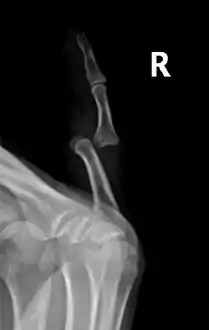

Radiograph of left index finger dislocation